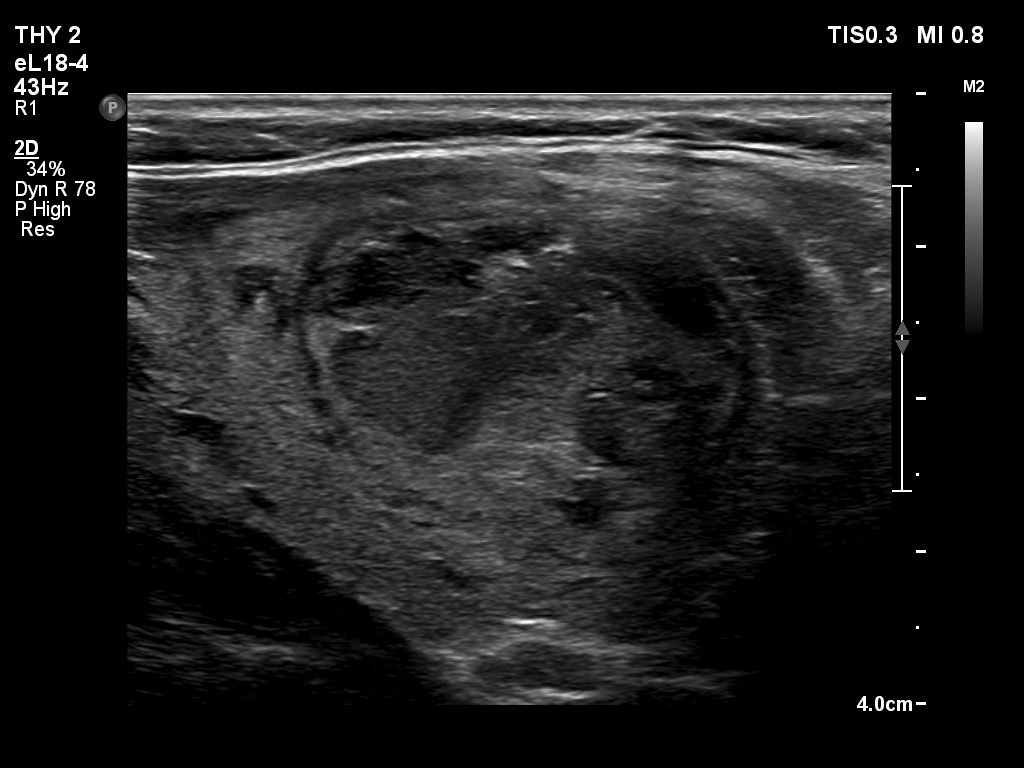

Ultrasonography. The thyroid was echonormal. The right lobe contained several discrete areas without any clinical significance. There was multi-chambered cystic nodule in the left lobe. The nodule had echonormal solid part and presented halo sign.

- The distinction between a multi-chambered cyst and a spongiform cyst is important, because in the latter the risk of malignancy is practically zero. In spongiform cysts almost the entire nodule is composed of cystic areas, and there is very small proportion of solid areas.

- The cyst has just started refilling after the evacuation.